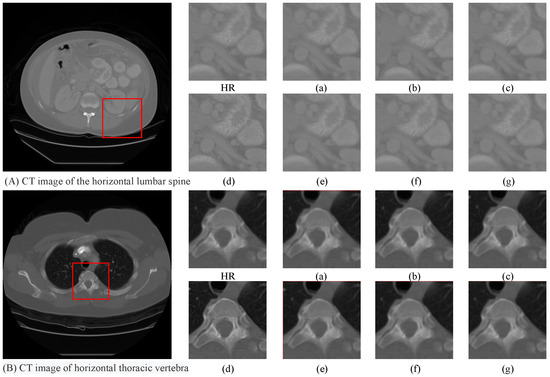

4.5. Ablation Study

- (a)

- “baseline” represents the basic model without the LAFE, CSAR, and .

- (b)

- “baseline + LAFE” refers to the “baseline” with the LAFE module.

- (c)

- “baseline + CSAR” denotes the “baseline” with the CSAR module.

- (d)

- “baseline + LAFE + CSAR” represents the “baseline” with the LAFE module and CSAR module.

- (e)

- “baseline + LAFE + ” refers to the “baseline” with the LAFE module and .

- (f)

- “baseline + CSAR + ” denotes the “baseline” with the CSAR module and .

- (g)

- “baseline + LAFE + CSAR + ” represents the final GAMA.